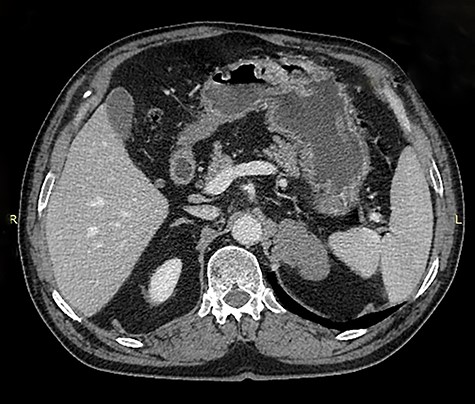

Because of its relatively large size and the patient’s request, he underwent a laparoscopic transperitoneal left adrenalectomy in the right lateral decubitus position (two 10-mm and one 5-mm ports). Intraoperatively, an enlarged left adrenal gland and a cystic lesion closely adherent to it were found, surrounded by adipose tissue (Figs 3 and 4). They were completely resected en bloc and removed in the endobag. No adverse events occurred postoperatively and he was discharged on Day 3.

Laparoscopic en bloc resection of the retroperitoneal cystic lesion adherent to the left adrenal gland and adipose tissue.